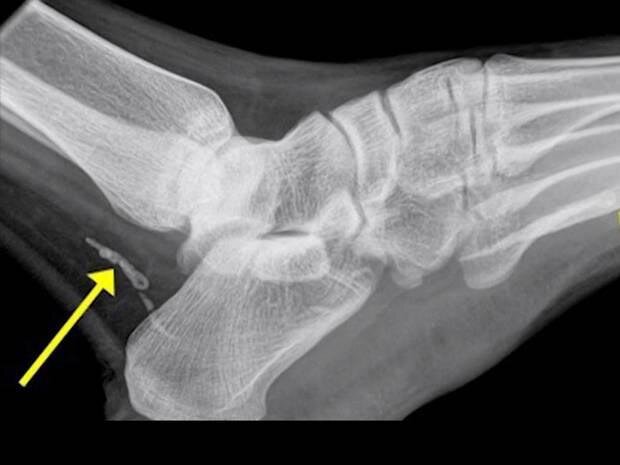

Вместо инфекции, в ноге африканца находился червь-паразит, известный как дракункулёз, или ришта. Личинки этого червя могут проникнуть в организм вместе с питьевой водой. Скорее всего паразит попал в организм африканца ещё до его отъезда в Австралию. На данном снимке вы можете видеть червя, состоящего из двух частей, которые отмечены на снимке желтыми стрелками. Обычно ришта вырастают до определенных размеров, разрывают кожу и вылазят на поверхность, но этот парень решил умереть в организме носителя и ествественно стал разлагаться

К счастью, врачи смогли быстро установить точный диагноз и быстро отправили африканца на операцию. Хирурги удалили остатки червя из ноги мужчины и он быстро пошел на поправку